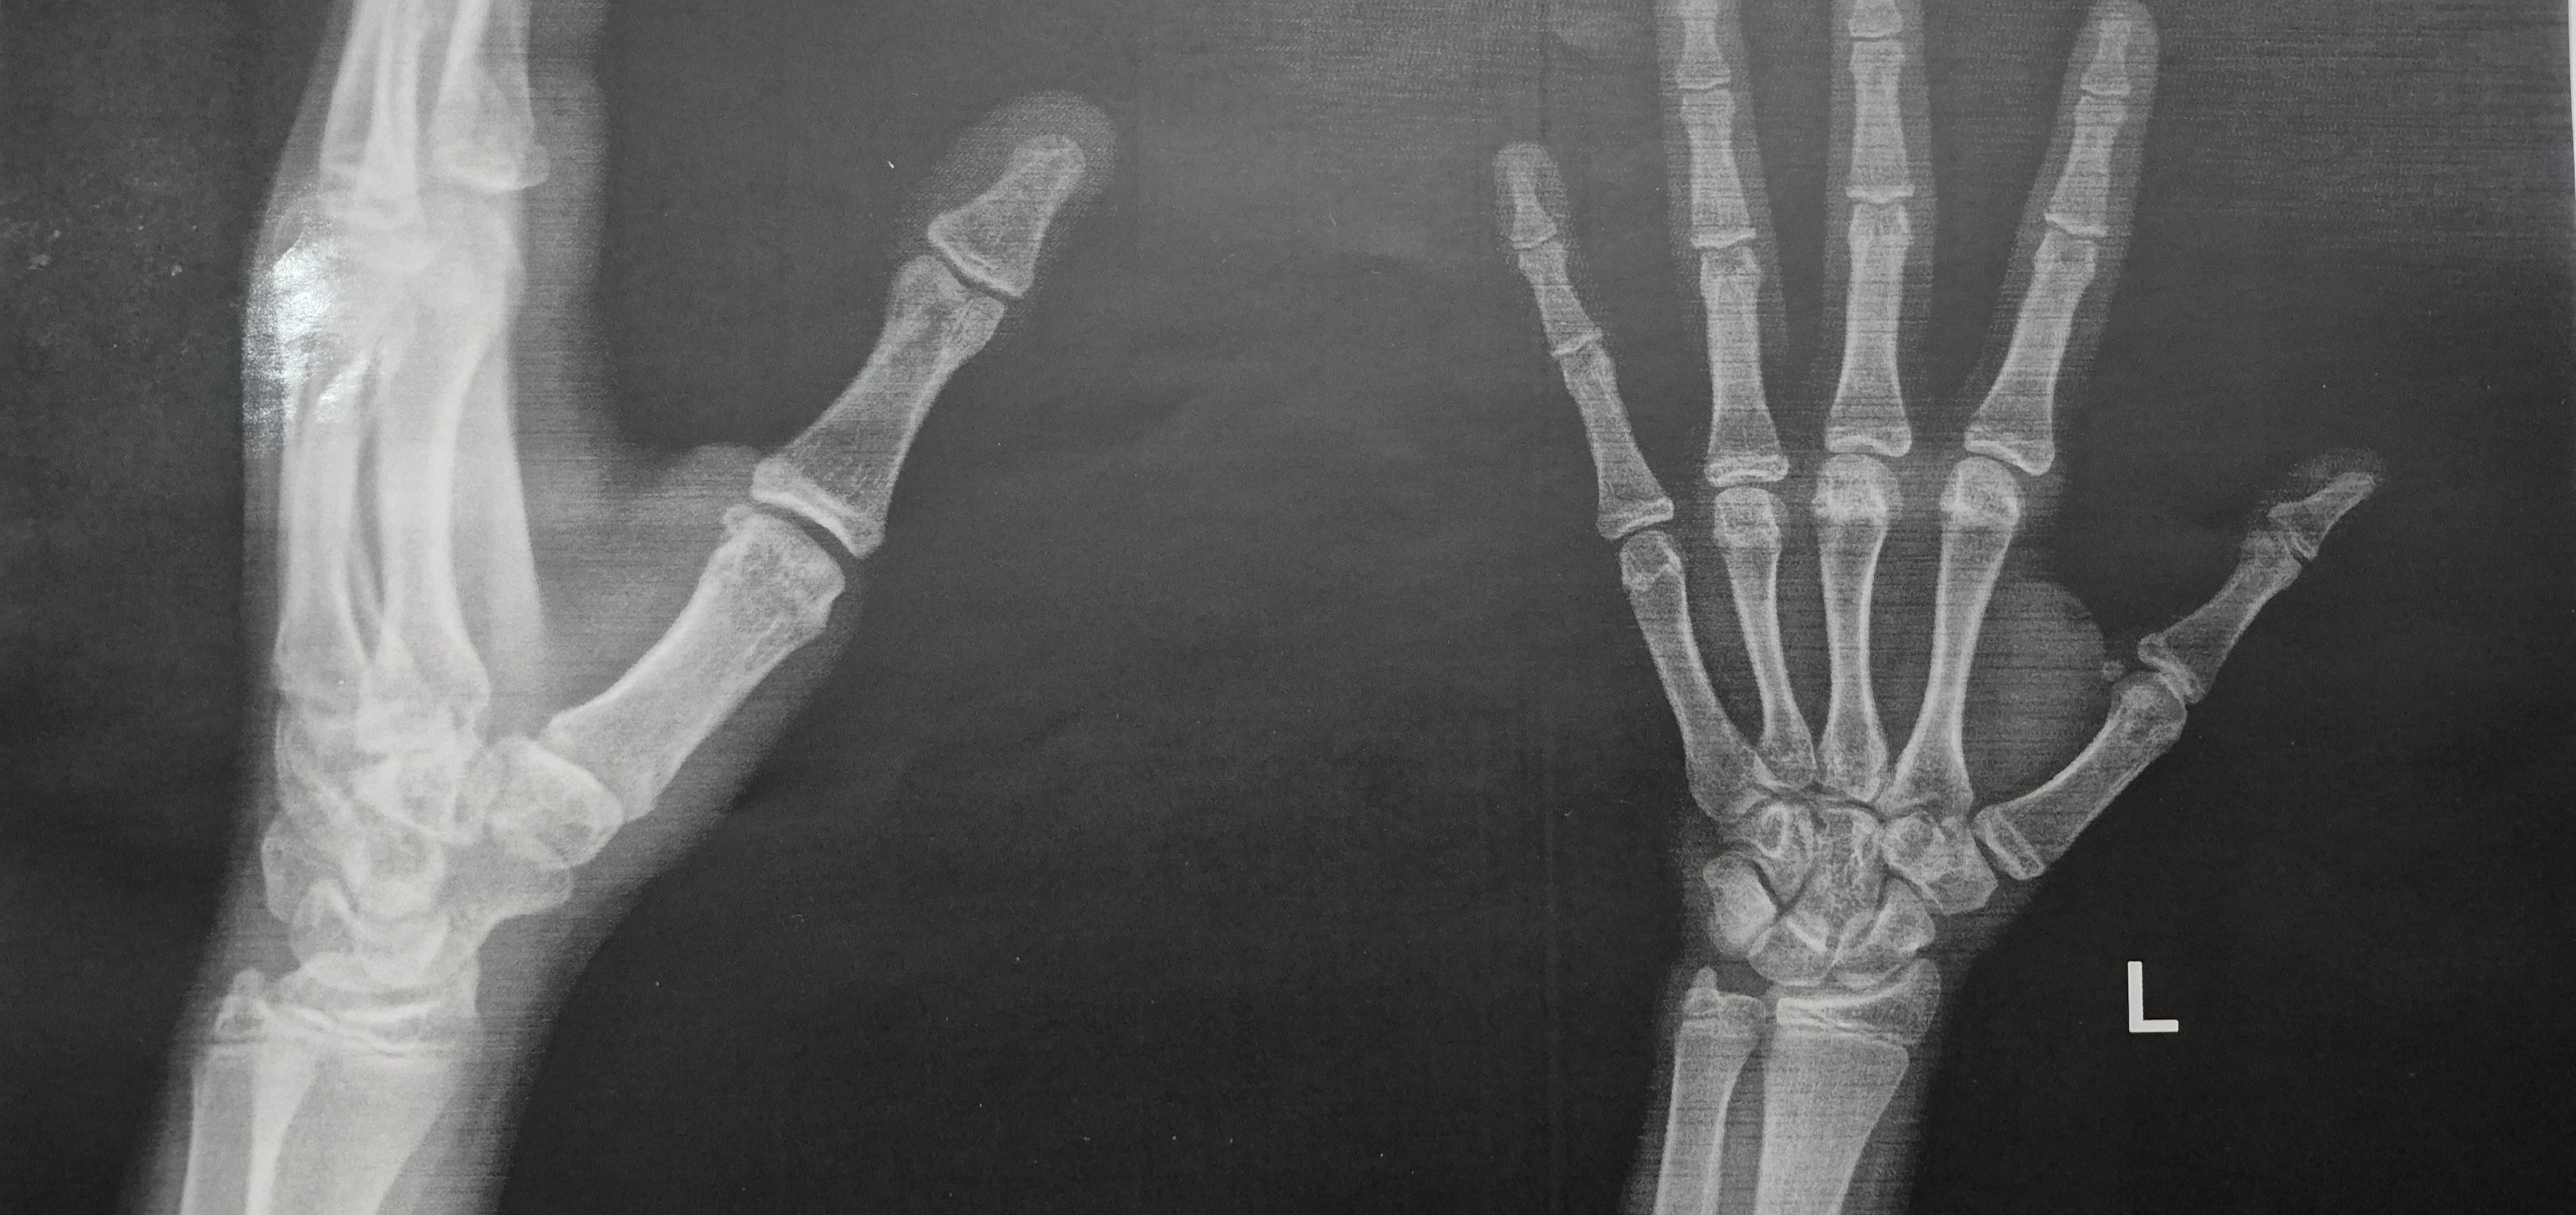

با توجه به عکس تا چند سانت قد رشد میکنه؟

شیرین سن : 20 وزن : 45 قد : 153

دختر هستم ۱۳سال و نیم قدم ۱۵۶ قد مامانم ۱۵۸ قد بابام ۱۷۰ والیبالو حرفه ای دنبال میکنم با توجه به عکس صفحه رشد مچ دستم تا چند سانت میتونم رشد کنم؟

سلام شیرین عزیز. در این مورد باید ویزیت ثبت کنید. ویزیت آنلاین با ارتوپد بگیرید و عکس را براشون در صفحه ویزیت ارسال کنید.